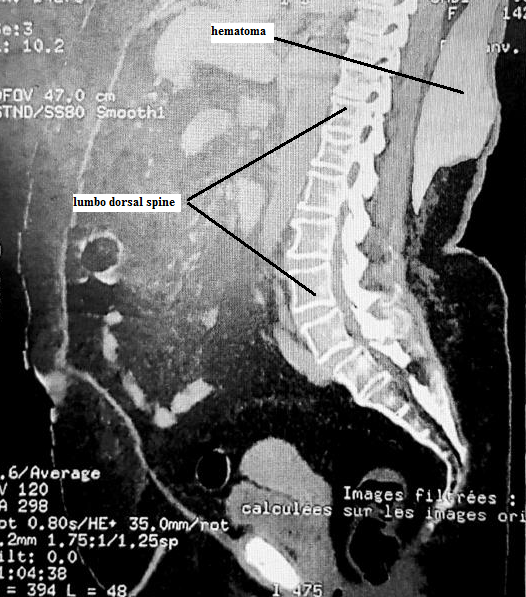

A 45-year-old female, obese with a BMI of 39.5 was scheduled to undergo hysteroscopy for endometrial hyperplasia under spinal anesthesia. She was diagnosed with well controlled diabetes and hypertension. She took neither antiaggregant nor anticoagulants and biological values were normal. In the operating theater, in sitting position, we could not detect the spinous process so we used the line of iliac crests as landmark for the level L4-L5. After several unsuccessful attempts to perform the spinal anesthesia at different levels, a swelling rapidly progressive and extensive appeared at the points of puncture. The intervention was reported and immediate lumbar scan showed a big subcutaneous hematoma in front of the last thoracic vertebras measuring 12x28x20 cm. Hemodynamic values, hemoglobin and the size of the hematoma remained stable and surgical abstention was decided. Hematoma was caused by probable injury of the posterior branch of spinal artery, favored by difficult spinal anesthesia for patient obesity and lumbar hyperlordosis, hence the interest of ultrasound localization both for level L4-L5 and for spinous process in obese patient. Three weeks later, hematoma was completely resolved and hysteroscopy performed under general anesthesia. Biopsy revealed endometrial adenocarcinoma.